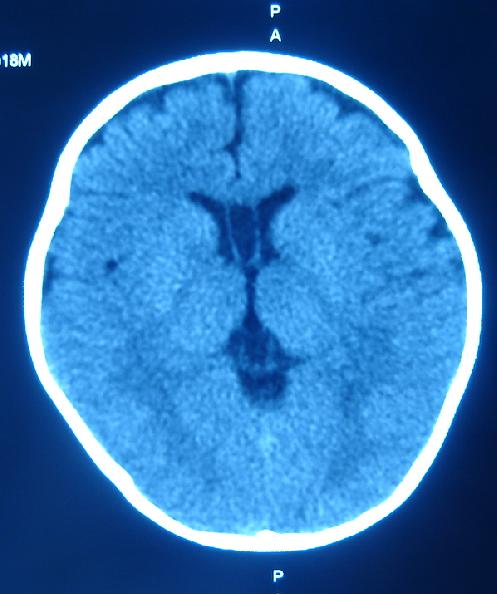

箭头指的地方是占位还是正常的直窦或正常组织?急!谢谢各位老师。

1)箭头所指:galen静脉(即大脑大静脉)。2)透明隔间腔与vergae腔并存。

1)箭头所指:galen静脉(即大脑大静脉)。2)第五脑室、第六脑室。